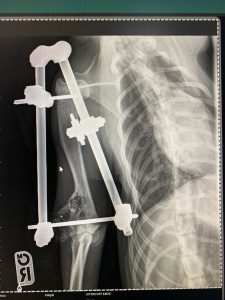

- Liječenje rupture prednjeg križnog ligamenta koljena TPLO (eng. Tibial Plateau Leveling Osteotomy)